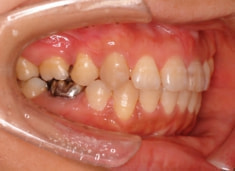

治療前